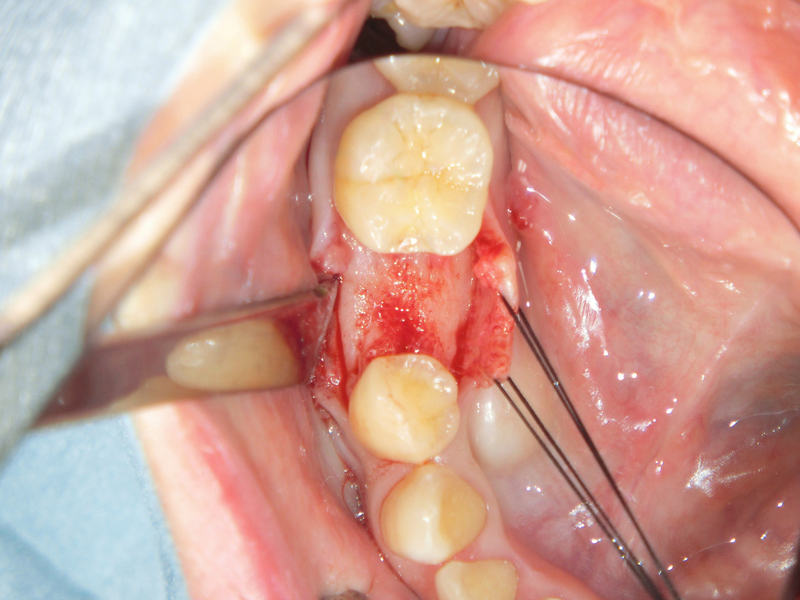

④一次手術(インプラント埋入)

麻酔を使用し、顎の骨に穴をあけてインプラント(人工歯根)を埋め込みます。インプラントの素材には顎の骨や歯茎、粘膜と適合性が高いと言われている純チタンを使用します。